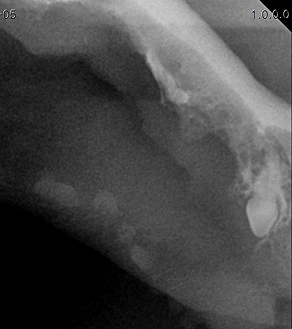

치주염 치료는 진행 단계에 따라 다르게 접근합니다.

BEFORE

AFTER